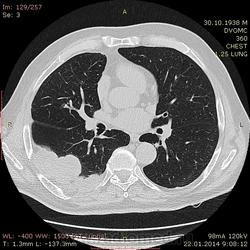

75 лет. Нарастающие боли в грудной клетке в течение 3х месяцев - со слов больного. Сейчас боль постоянная. Температуры небыло. Кашля нет. Беспокоит боль и слабость.

Плотность многоузлового образования у задней стенки от жидкостной до мягкотканной. Осумкованный плеврит или образование? Или и то и другое? Или вообще другое? Очень жду Ваших мнений.

Вопрос сложный сказать трудно, и без контрастирования трудно, и после контрастирования вопросы (скорее всего) останутся. На мой взгляд,  жидкостно-солидное образования  и осумкованные гидротораксы справа. Это может быть и первичное образование легкого, например Pulmonary Adenoid Cystic Carcinoma http://www.jkscience.org/archive/volume141/Primary%20Pulmonary%20Adenoid%20Cystic%20Carcinoma%20with%20Lumbar%20Vertebral%20Metastasis%20Response%20to%20Gefitinib.pdf но могут быть и  метастазы какой-нибуль кистозной опухоли, например, околоушной железы.

А может быть сзади это мезотелиома?

К сожалению сейчас нет возможности перевести изображения из дайкома в картинки. На словах скажу, что логично пунктировать центральный отдел образований. Заключение: КТ-признаки пристеночного объемного образования правой половины грудной полости (более вероятно новообразование, исходящее из плевры).